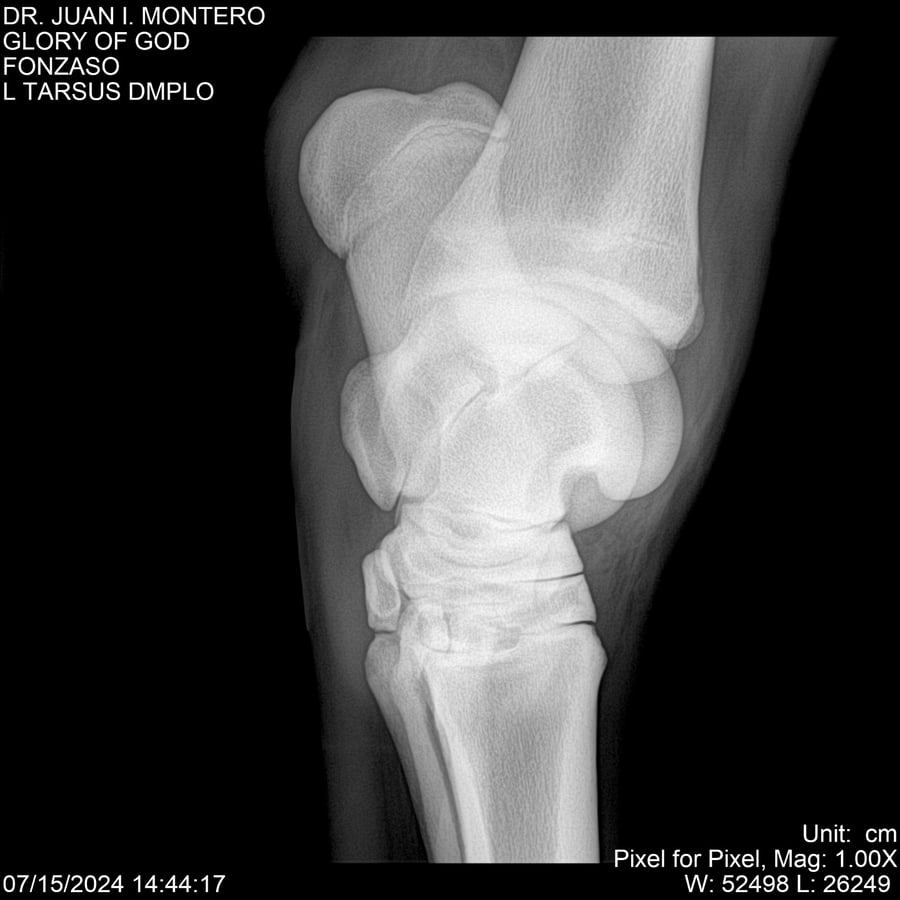

LOTE 10, GLORY OF GOD 🔥 🔥 🔥 Lote Anterior Volver al remate Lote Siguiente Ficha Contacto Montevideo - Ficha del Lote Identificador: #281389 Categoría: Yeguarizos Montevideo - 115 Visualizaciones ClicData Contacto Empresa: Abelenda N. R., Walter Hugo Nombre*: Teléfono* : E-mail* : Mensaje Enviar Registrese gratis Este contenido Exclusivo está disponible sólo para usuarios registrados Ingresar